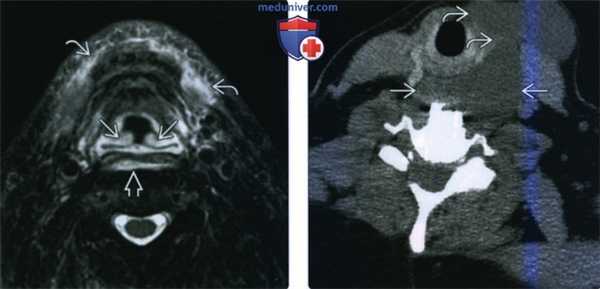

(Слева) При КТ с КУ у пациента с жлобами на боли в области шеи определяется умеренное расширение ЗГП за счет жидкостного содержимого низкой плотности. У пациента диагностирован тендинит длинной мышцы шеи. Обратите внимание, что левая длинная мышца шеи несколько увеличена, плотность ее понижена, а контуры менее четкие. Впрочем, подобные изменения обнаружить непросто. Признаков тромбоза внутренней яремной вены или отека глубоких клетчаточных пространств шеи нет.

(Справа) КТ с КУ, сагиттальная реконструкция. Неоднородные кальцификаты кпереди от атлантоосевого сустава, являются признаком острого тендинита длинной мышцы шеи. Отмечается небольшой отек ЗГП.